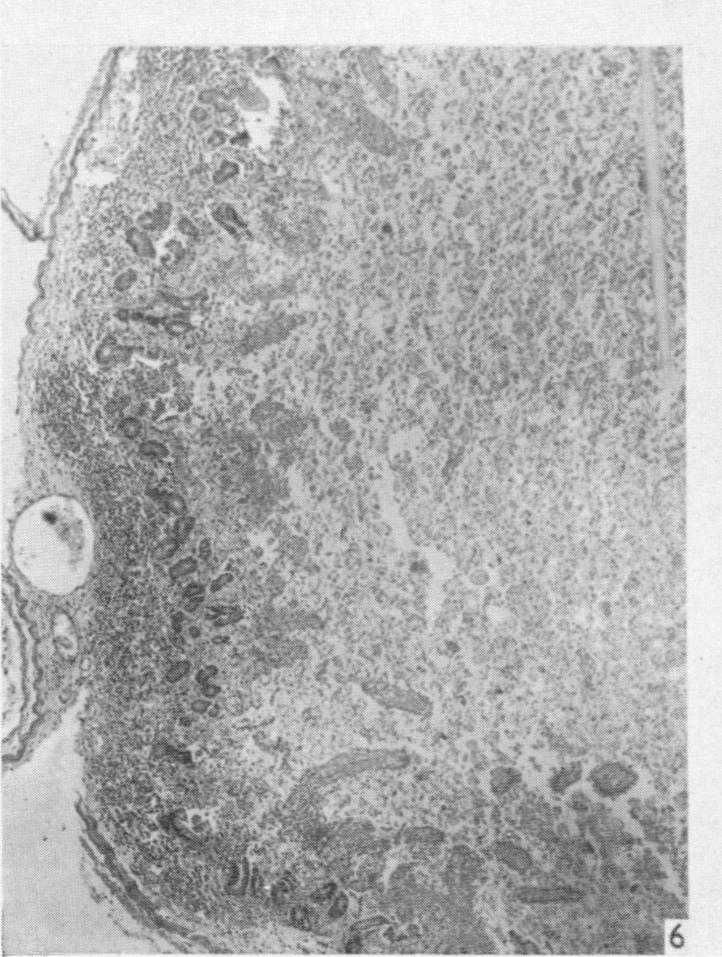

The experimental reproduction of enterotoxaemia in piglets.

J Hyg (Lond). 1959 Mar;57(1):81-91. doi: 10.1017/s0022172400019914.